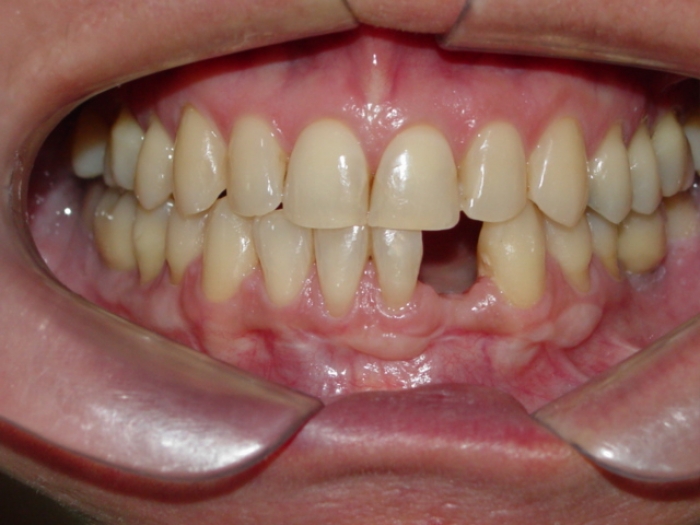

Raio X inicial